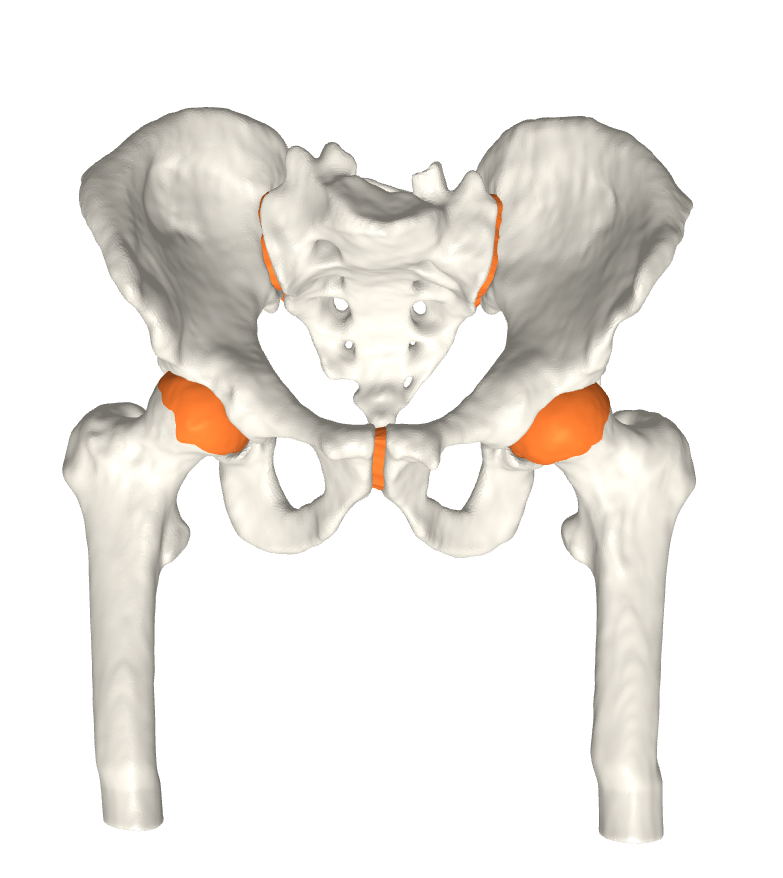

We have qualitatively verified that the articulating surfaces in all the ten HJs are detected correctly regardless of their anatomical variance using visual inspection of overlays as shown in Fig. 4. As desired, we observe a high degree of congruence between the opposing joint surfaces, meaning no gaps or overlaps in the cartilage-cartilage interface. Moreover, we observe a smooth transition towards the bone geometries as expected from the correct anatomy. The parameter values used to generate the cartilage from Fig. 5(a). The free parameters are the neighbourhood-size used to estimate the curvature of the bone (𝒩𝒩\mathcal{N}); the minimum and maximum curvature in the cartilage region (κmin,κmaxsubscript𝜅subscript𝜅\kappa_{\min},\kappa_{\max}; Eq. (2)); the distance parameter in mm𝑚𝑚mm (δ𝛿\delta; Eq. 1); and the number of times the outer boundary should be trimmed (Ntrimsubscript𝑁𝑡𝑟𝑖𝑚N_{trim}). Here, the curvature based parameters (𝒩,κmin,κmax)\mathcal{N},\kappa_{\min},\kappa_{\max}) are only used for the femur. See supplementary material for more visual comparisons.

Fig. 4 visualizes the von Mises stress pattern on the pelvic cartilage for one HJ. More are shown in the supplementary material. We have verified that no spurious stress peaks appear and that stress values change gradually and smoothly across the cartilage. Further, the high-stress areas are located in the up-direction, as we expect from the applied displacements. The stress values and patterns are not to be confused with those from a real stance. They only serve as a verification test of simulation properties. For such a simulation, we require ligaments and muscles to stabilize the girdle and a correction from sublime pose bias.

(b) CT scan overlay.

Figure 4: The von Mises stress patterns ((a)) and the generated cartilage imposed on the CT scan from which the bone was extracted ((b)). Notice the high level of congruence in the cartilage-bone interfaces and cartilage-cartilage interface.